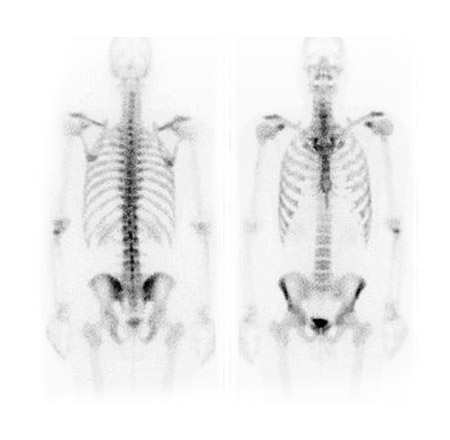

Diagnostic nuclear medicine is a specialized form of medical imaging that evaluates how organs and tissues function. Unlike imaging exams such as X-ray or ultrasound that primarily show anatomy, nuclear medicine imaging provides information about physiological activity, helping detect disease or injury at an early stage.

A specialized camera, called a gamma camera, detects this radiation to create images. Imaging is painless and usually involves lying still on an examination table while the camera is positioned close to your body.